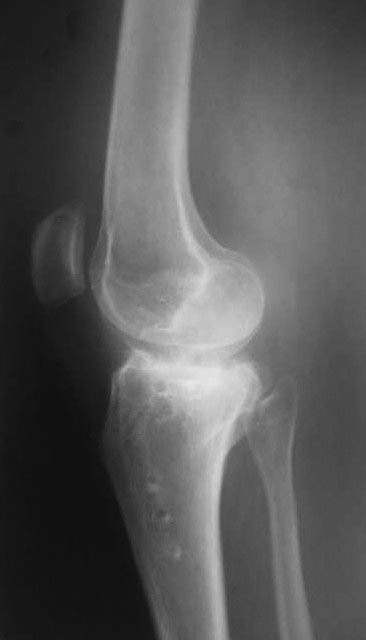

Жалобы на деформацию и нарушение функции правого коленного сустава .Внешний вид –вальгусная деформация на уровне коленного сустава .Коленный сустав стабильный, надколенник при сгибании в правильном положении.

Планируэм провести остеотомию на уровне проксимального метафиза большеберцовой кости .

Вложение не в текстовом формате было извлечено…

Имя     : IMG_0040.jpg

Тип     : image/jpg

Размер  : 64740 байтов

Описание: отсутствует

Url     : http://weborto.net:8080/pipermail/ortho/attachments/20120513/91cb8573/attachment-0004.jpg